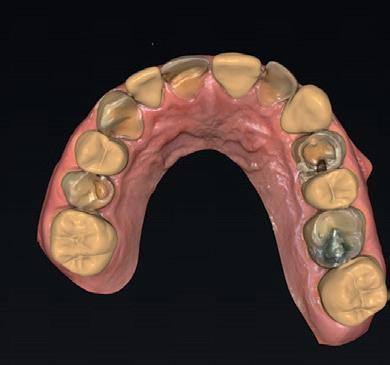

Mevrouw X (afbeelding 1) meldt zich met een desolate dentitie in de bovenkaak en een duidelijke wens voor een vaste voorziening na extractie. Diagnostische gegevens worden verzameld via fotografie, CBCT (Sidexis), een 3D-scan (3Shape) en een digitale facebow-registratie (MODJAW). Al deze gegevens worden samengebracht in SmileCloud, waar behan-

delaren, tandtechnici en ondersteunend personeel toegang hebben tot het dossier en gemakkelijk kunnen overleggen.

SmileCloud maakt het mogelijk om een voorstel (mock-up) uit de DSD-database te genereren dat per tand kan worden gepersonaliseerd (afbeelding 2a en b). Zodra het restauratieve einddoel duidelijk is, kan de implantologie worden gepland. Voor een esthetisch resultaat zijn bothoogte, gingivale dikte en het ontwerp van de tijdelijke restauratie cruciaal. Hier biedt het VEX-model uitkomst (afbeelding 3a-c). Dit model (Virtual Extraction Model) maakt het mogelijk om het implantaat, het abutment én de restauratie virtueel in te plannen. Zo kun je bijvoorbeeld zones van overdruk of onderdruk herkennen, problemen met de gingiva voorzien, het emergence profile